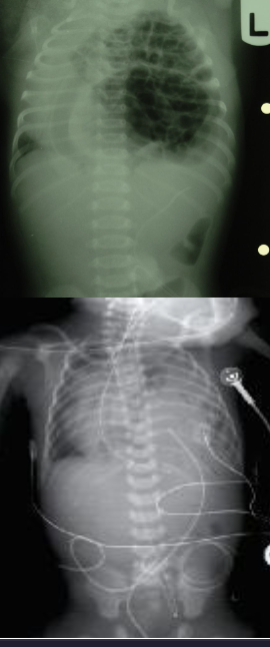

Case: Preterm Infant with Respiratory Distress

- Preterm 29 weeks gestation C/S delivery showed severe respiratory distress soon after birth - RDS

- Air bronchograms

There is a homogeneous opacification of both lungs with white-out lungs - (1 .field (grounds glass appearance) and air bronchogram bilaterally

.The diagnosis is Acute Respiratory Distress Syndrome (ARDS) - (2

- .I- Massive blood transfusions Preterm 29-weeks gestation C/S delivery showed severe respiratory distress soon after birth. This chest x-ray was taken at the age of 6 hours.

- Q1: Write 2 abnormalities in the X-Ray?

- Q2: What is the likely diagnosis?

- Q3: Write 2 management steps.

Answers:

- Q1: Ground glass appearance, wide intercostal space.

- Q3: Mechanical ventilation, give Surfactant for lungs maturation.

What are the possible diagnoses? Congenital pneumonia or respiratory distress.